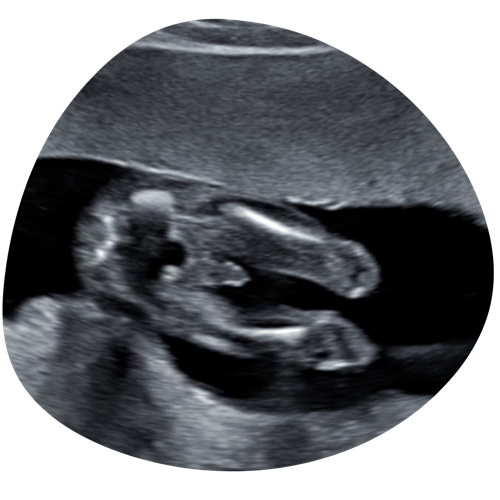

2D echo

Tijdens je hele zwangerschap kunnen we je kindje in 2D laten zien. We kunnen met 2D goed naar de structuren in het lichaampje van je kindje kijken en naar bijvoorbeeld het profieltje, handjes, voetjes etc. Geef vooral aan wat jullie graag willen zien!

€35 (15 minuten)